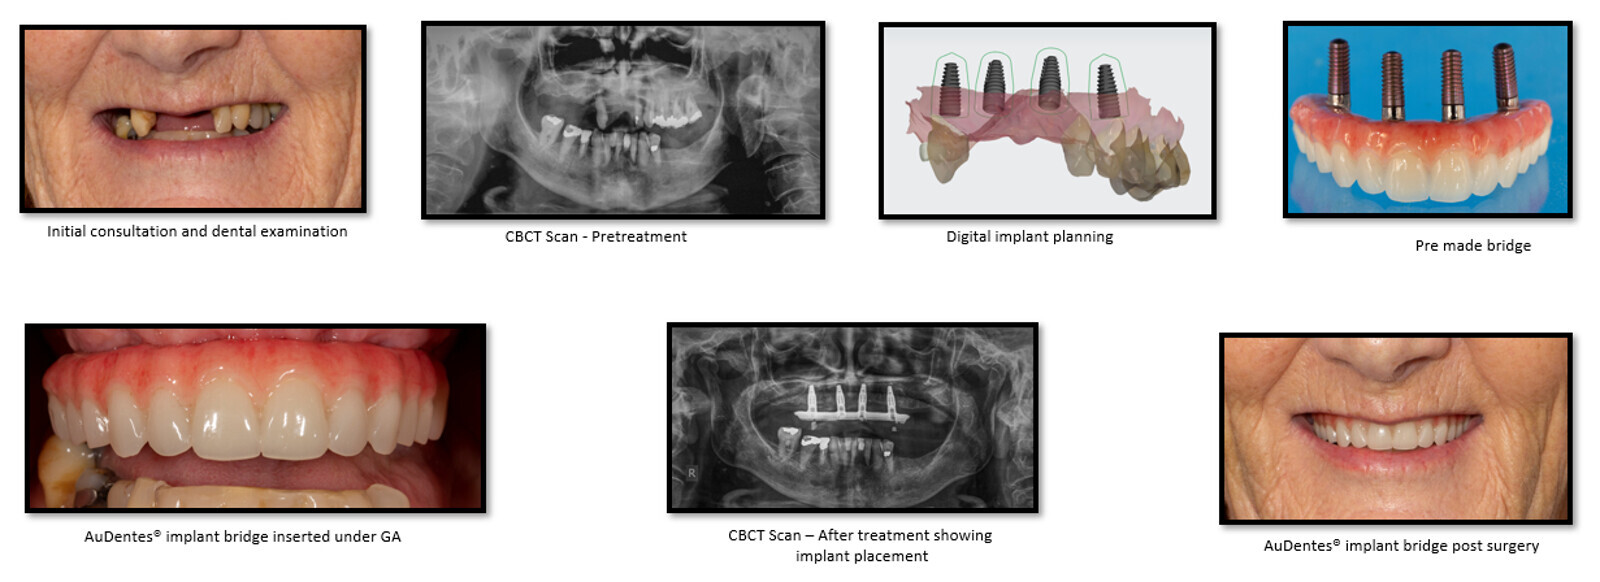

Could you explain the exact surgical procedure? The first step is to make sure that we understand what the patient wants and needs. Therefore, we do a diagnostic wax-up—except it is not a real wax-up; it is all virtual. We take an intra-oral scan, photos and videos, and we do a virtual set-up so that we can establish what the patient wants. The second step is to get a CT scan and merge all the information of where the teeth are now and where the teeth should be. After that, we can plan the implants and the prosthesis. The third stage is the treatment, for which the patient usually receives some sedation or general anaesthetic. During the surgery, we extract the teeth, recontour the bone, place the implants using guided surgery and then screw the prosthesis in. This is all done in one visit. Two or three days later, we check the situation and then check again after two or three months and torque the implants.

Treatment path of the AuDentes implant-retained prosthesis. (Image: Philip Tan)